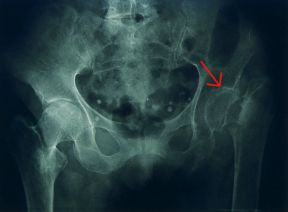

Radiografia del bacino. Bacino. La radiografia mette in rilievo l'osteoporosi a carico delle ossa del bacino. Sono visibili le alterazioni degenerative dovute all'insufficiente elaborazione della matrice proteica (freccia).